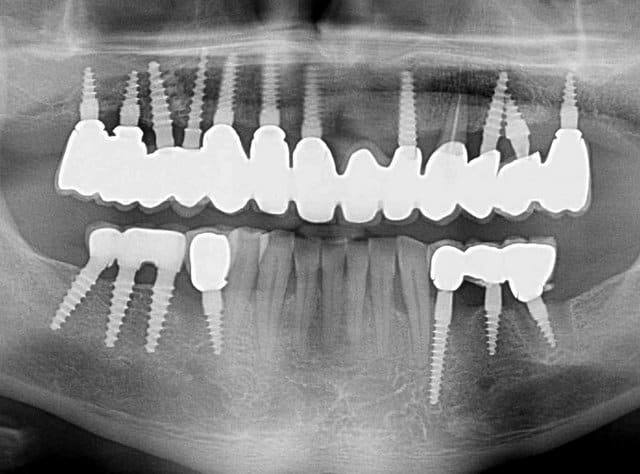

23 implants, rehabilitation totale

Bonjour flicflac je suis désolé de ma réponse tardive, oui il est vrai que ce n est pas beaucoup documenté ... je serai un menteur de dire que que je n ai jamais perdu des implants, surtout entre la 2eme et 8eme semaine après l implantation.Un échec vraiment à cause de la perte osseuse et avec le même process cela est arrivé une fois avec une madame, où l´os était encore infecté ( avant la chirurgie),mais après l ´échec (c était à la position 35) on a pu laisser le bridge. Malheureusement je n ai pas toutes les photos ici à Mallorque sur mon PC portable. Ci dessous une photo après 10 ans 46 47 et les implants au maxillaire.

Oui ca semble ....sur la opg radio tu peux voir la situation seulement deux semaines après l´implantation immédiate 34 jusqu´à 36 et 45, les derniers 2 photos montrent la même situation après un an ( où on a enlevé la supra construction pour un contrôle). Sur ce cas je voulais montrer la bonne régénération osseuse et de la gencive.